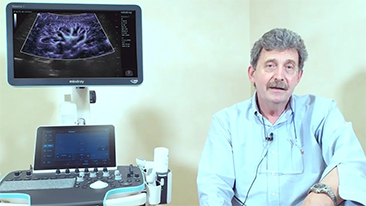

Covid-19 - Pr├│ba si? dla ludzi i aparatury

W zwi?zku z pandemi? koronawirusa szpitale i personel medyczny opracowa?y nowe praktyki robocze obejmuj?ce post?powanie w sytuacjach dotycz?cych stanów ostrych, dystans spo?eczny, rygorystyczne stosowanie ?rodków ochrony indywidualnej (?OI), mycie r?k i codzienn? dezynfekcj? sprz?tu. Dodatkowo w punktach opieki medycznej coraz wi?ksze znaczenie zacz?? mie? przeno?ny, wysoce mobilny i wszechstronny sprz?t, przydatny zw?aszcza w sytuacji, gdy oddzia?y i bloki operacyjne s? rozmieszczone na kilku pi?trach, a dost?p do specjalistycznych urz?dzeń jest ograniczony.